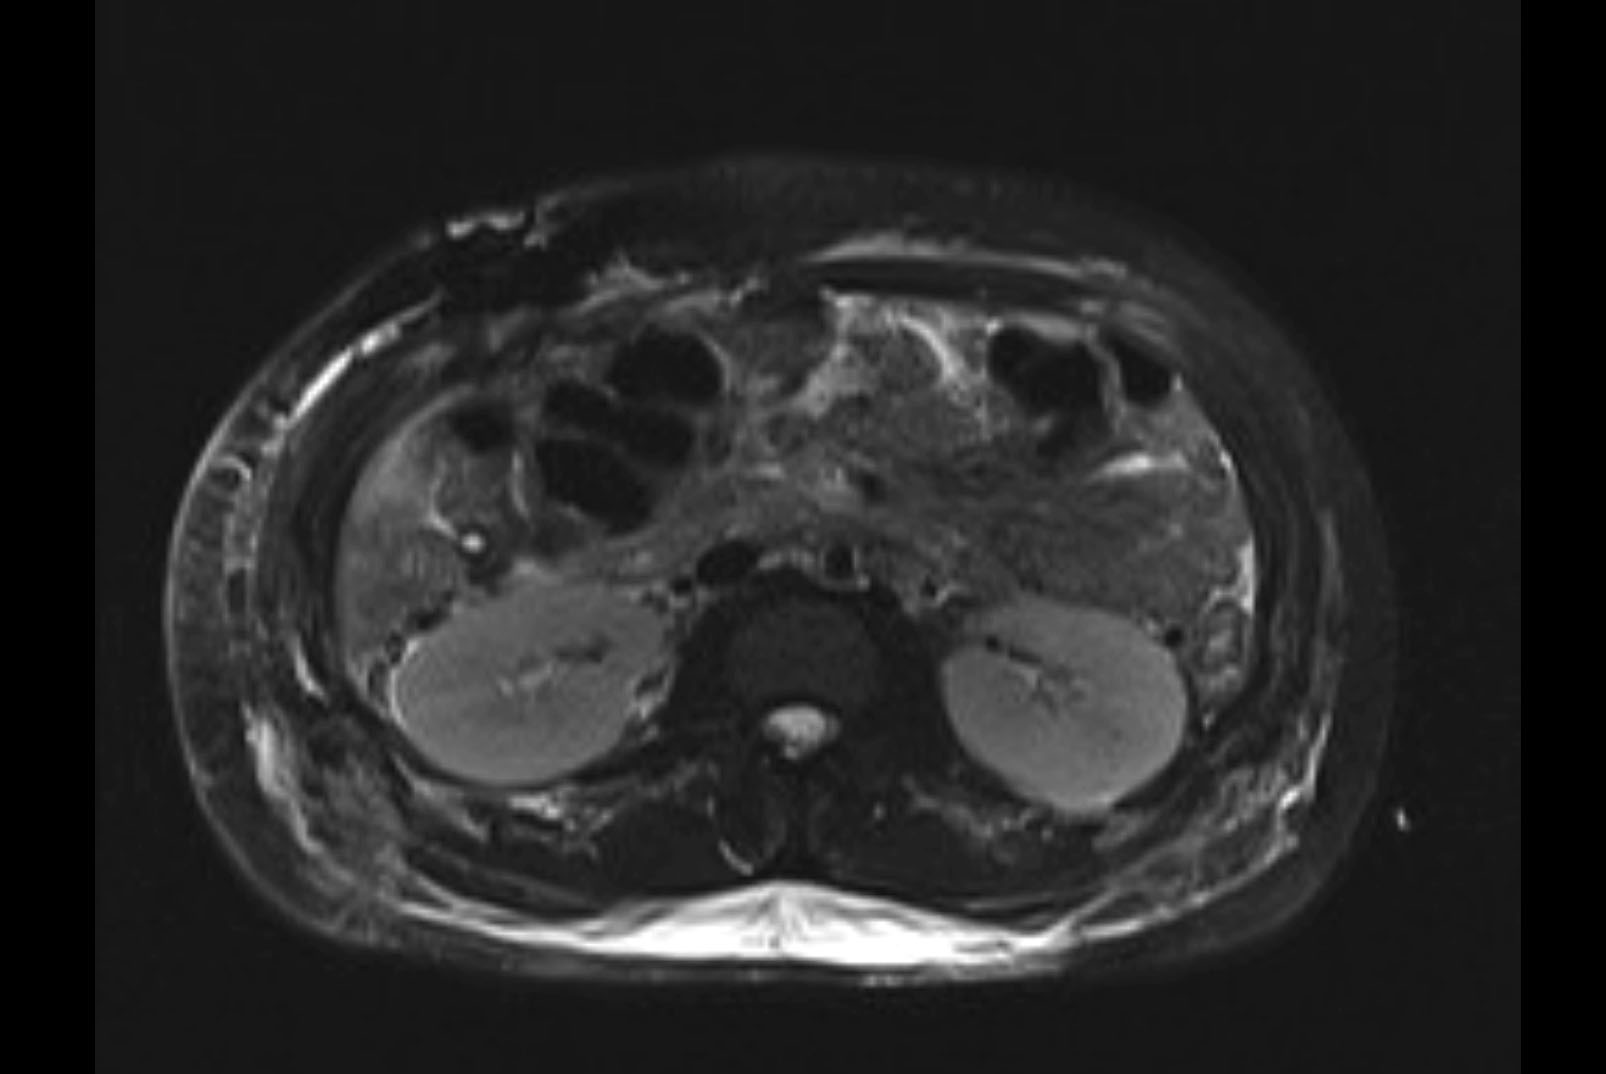

MRI T2